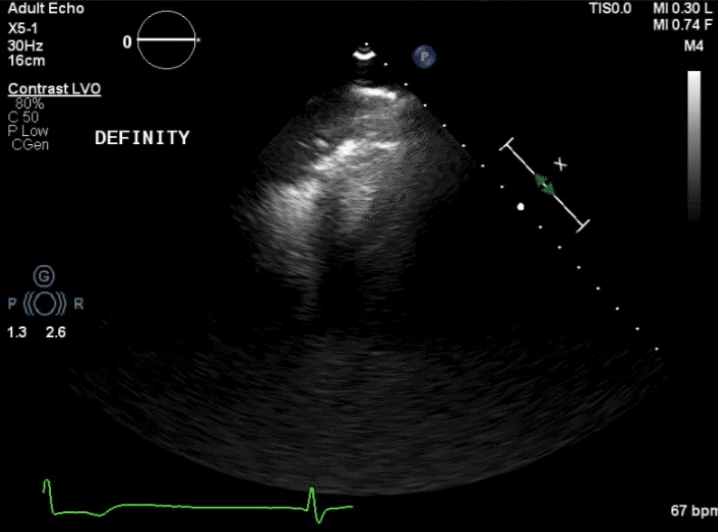

Figure 1. Initial angiography with severe stenosis of the proximal left anterior descending (blue arrow) (A). After intervention, a coronary artery perforation is seen in the distal vessel (blue arrow) (B). Transthoracic echocardiography showing the left ventricle and right ventricle (C). CEE after intracoronary injection of the UEA, the UEA is seen filling the right ventricle while notably absent from the pericardium (D).

After balloon tamponade, continued extravasation was present on angiography. CEE was performed with an intracoronary injection of an UEA. The UEA was seen filling the cardiac chambers, but no pericardial effusion was seen and there was no UEA identified filling the pericardial space (Figures 1C and 1D, Video 2). Together with the angiographic finding, we determined the perforation was likely into a coronary vein. No further intervention was performed. The patient remained hemodynamically stable and was later discharged without significant events.